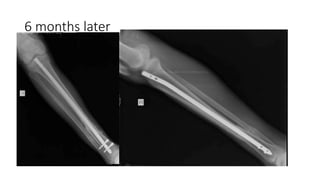

The document outlines a surgical procedure for treating malunion of the distal tibia, detailing steps that include applying an external fixator, performing an open reduction, and using fibular osteotomy. Key steps involve exposing the tibia, mobilizing and lengthening the fracture, and ensuring anatomic reduction during the insertion of a rod. The procedure emphasizes the importance of maintaining stability and avoiding proximal locking if possible.